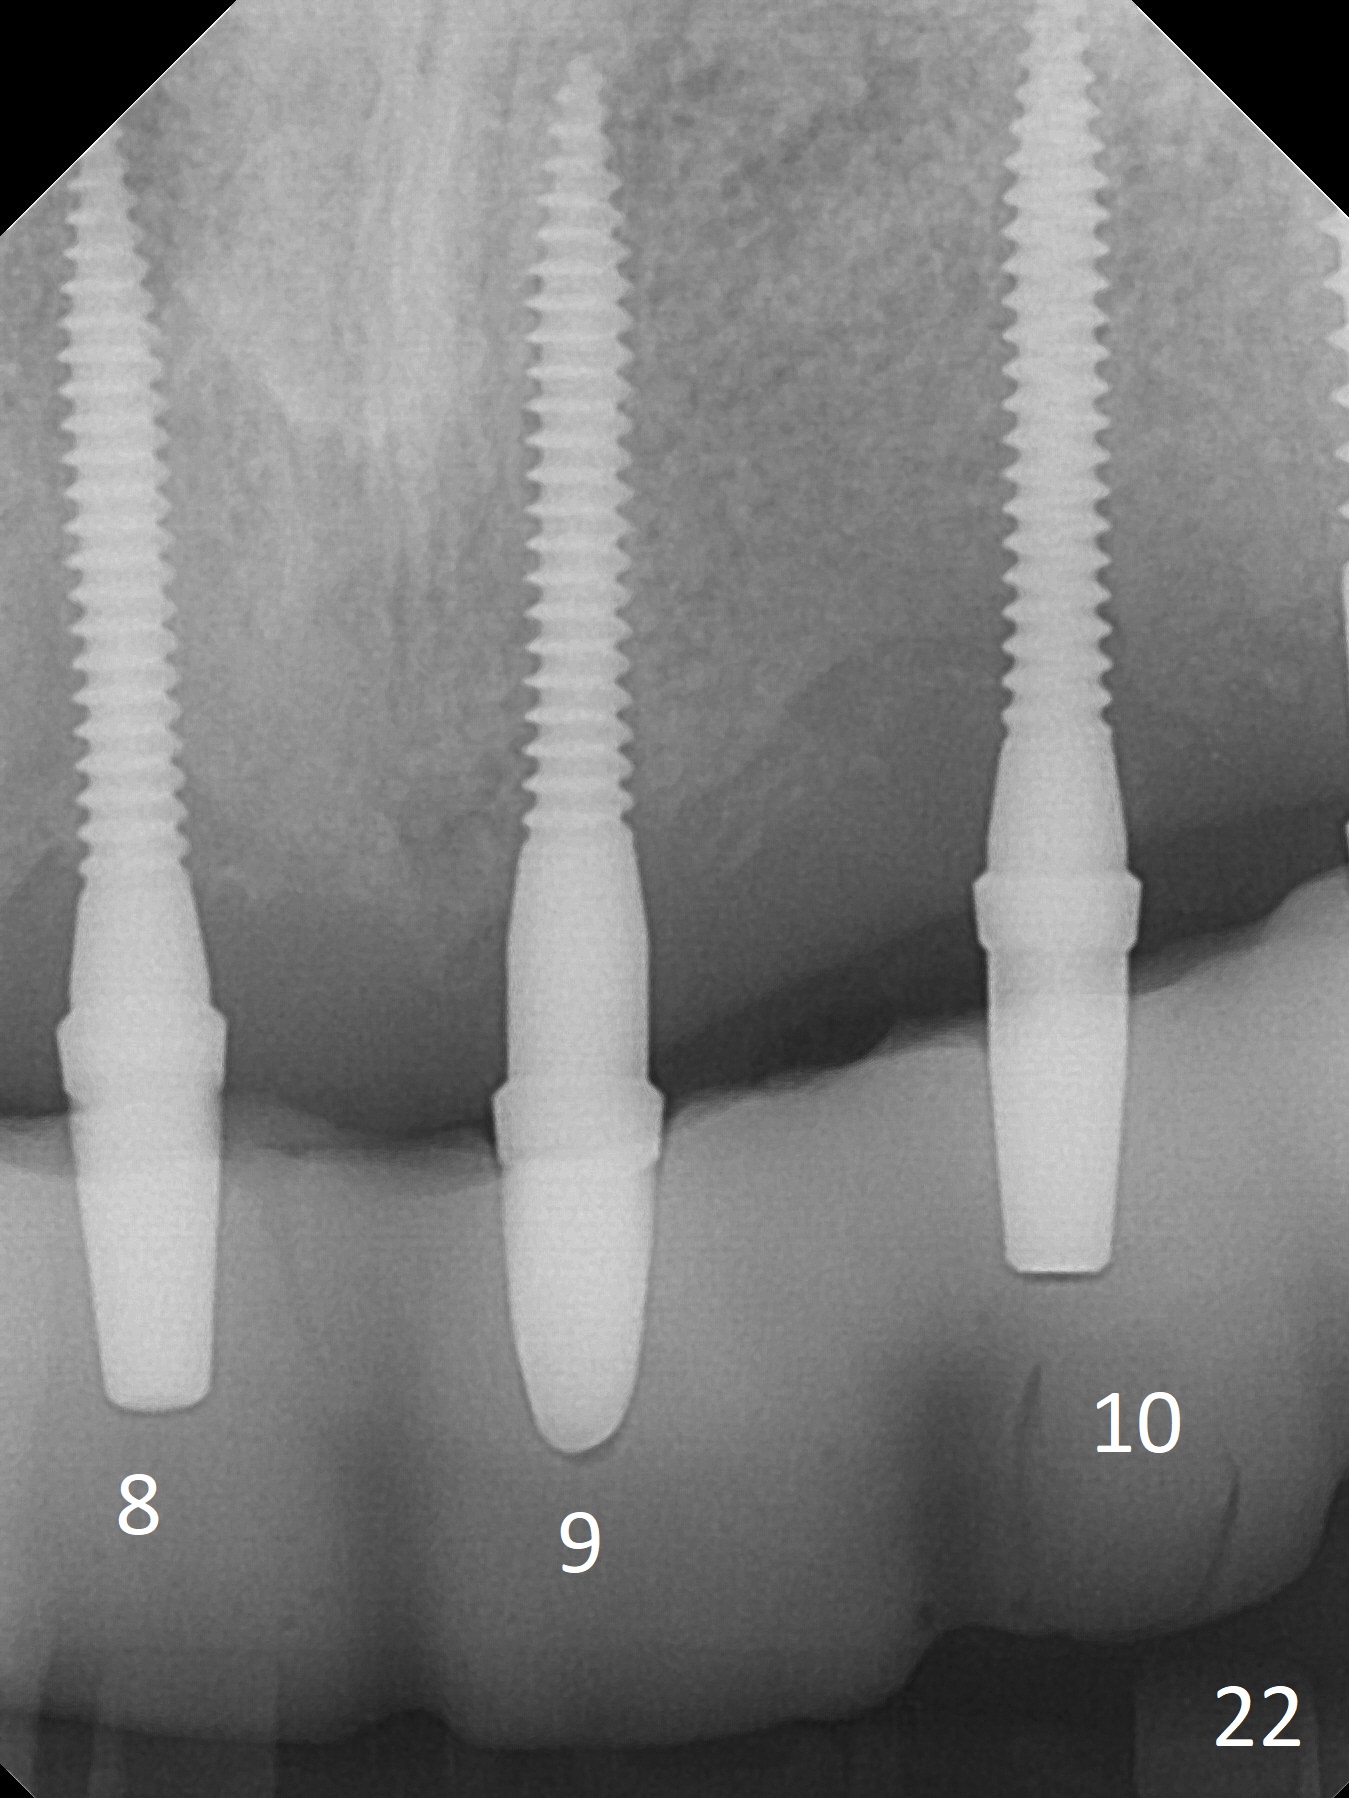

Three of 2x14(2) mm 1-piece implants are placed at #8-10 (Fig.6,11,12).   There is no bone loss nearly 4 months postop.